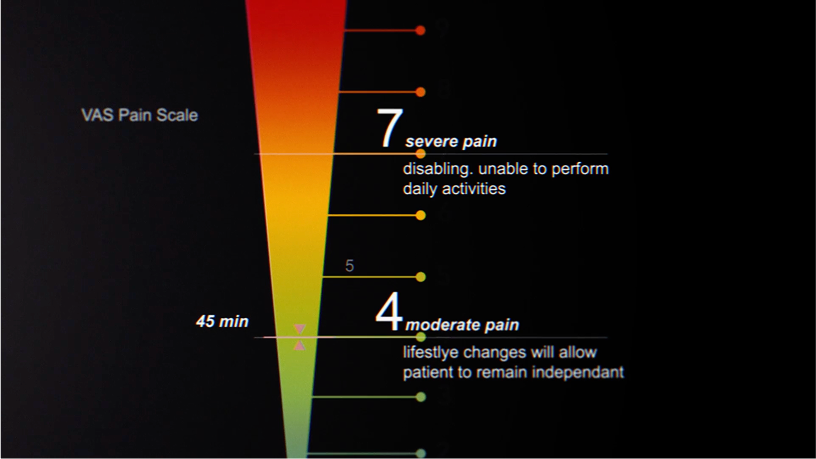

Using the clinical VAS Pain Scale, pain was reduced from an average of 7.1 to 4.0.

Reduced Inflammation For 94% of Patients!